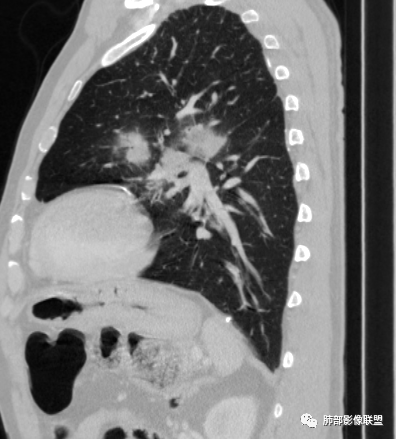

左肺上叶大肿块,膨胀性生长,边界清,密度较低,见部分坏死区,强化弱,肿块见支气管充气V扩张征,分布僵直,枯树枝特点,另一个重要特点血管造影征,淋巴瘤,肿块长轴与胸膜平行,与隐球菌鉴别,隐球荚膜抗原检查,明确诊断经皮肺穿刺。另胸膜钙化(问诊既往有无患胸膜炎病史)。

老年男性,糖尿病病史,消瘦、乏力三个月,影像表现左肺上叶胸膜下团块,有一定张力,内部疏松,可见支气管影及坏死区,增强病灶边缘环形强化,内部未见强化,考虑炎性肉芽肿病变,隐球?奴卡?放线菌?鉴别淋巴瘤。

左肺上叶胸膜下肿块,宽基底与胸膜相连,跨叶裂,边缘清晰膨隆,其内支气管充气,部分扩张、僵直,无明显强化,血管造影征,考虑淋巴瘤,鉴别腺癌

左肺胸膜下巨大占位,跨叶裂,宽基底与胸膜相连,胸膜钙化,平扫密度较低,强化不明显,可见内部血管显影,支气管充气征和扩张,考虑为恶性,倾向于淋巴瘤

大肿块,边缘光滑,深分叶

近端支气管堵塞、推移为主

部分类似于脐凹征

内部支气管扩张

肺动脉推移为主,边缘部分进入

大肿块、表面光滑但深分叶,肺门侧支气管堵塞

1)部位:周围型或中央型软组织肿块,以周围型为多见,且肿瘤多位于肺上叶。如本例:该肿瘤位于左肺上叶。

2)大小及形态:由于本病恶性程度高,早期症状不明显,发现时肿块均较大。如本例病变巨大。

3)肿块边界和边缘:多较清楚,呈圆形、类圆形,且由于肿块生长速度不均匀,可见分叶,毛刺少见。有报道肿块周围毛玻璃影是多形性癌特征表现。

4)密度:肿块平扫为软组织密度,由于体积较大,内部常见大片状坏死,可出现不规则厚壁空洞或坏死内多发无壁小空洞,坏死多不均匀:坏死灶内可见如柳絮样的斑片样强化灶,坏死边缘与非坏死区分界不清本例坏死较明显,密度不均匀。

5)肿瘤强化方式:肺部恶性肿瘤强化程度与其血供丰富程度相关,血供丰富多强化明显,反之则较差。由于PSC 周边实性部分富血供及内部黏液变性、坏死,增强后肿块多数呈轻-中度边缘环形强化或不均匀小斑片状强化。国外学者对照病理发现肿瘤细胞或胶原组织增强扫描时强化,无强化的低密度区代表了黏液样变性区和出血坏死区。